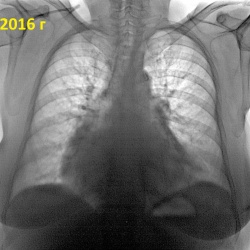

Добрый день, справа уменьшение объёма S3, инфильтрация,   подозрение на ЗНО бронха?